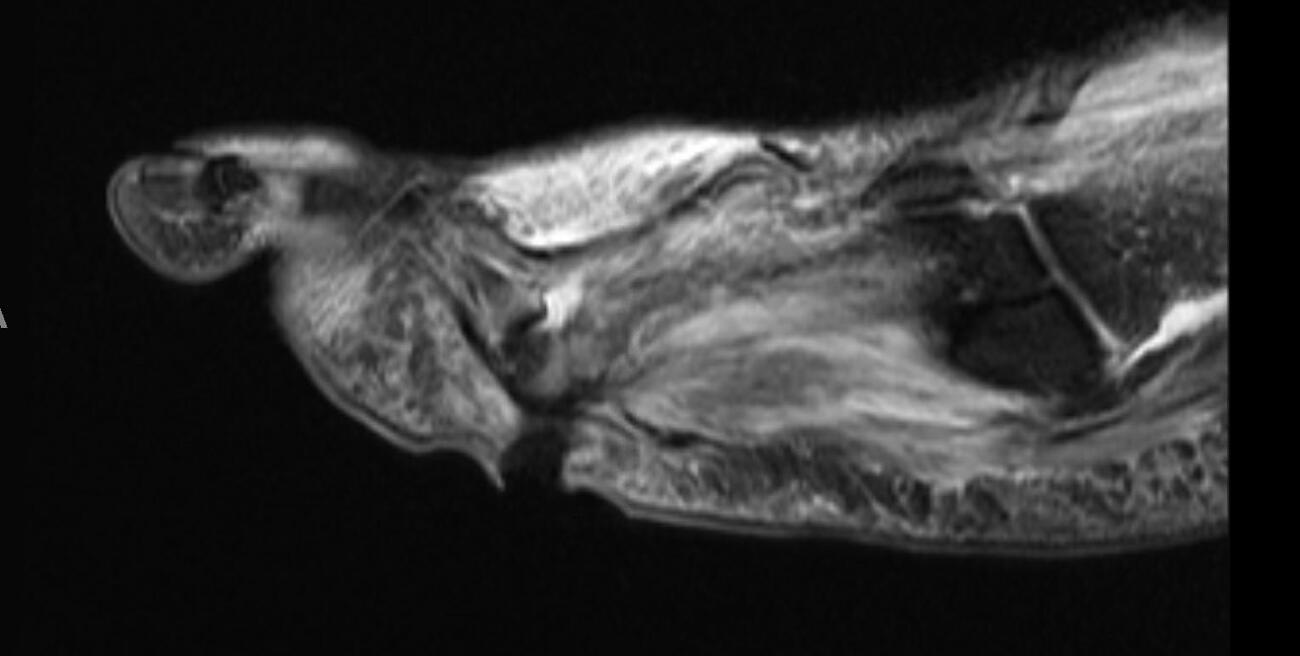

We present an unusual case of a 39-year-old male with poorly controlled type 2 diabetes, and status post-myocardial infarction, who presented to the ED with an infected chronic plantar right foot wound. There was no superficial dermatophytosis noted to the foot. He began empiric IV antibiotics, and a right foot MRI showed osteomyelitis of the bases of the fourth and fifth proximal phalanges as well as the head of the fourth metatarsal. He underwent initial irrigation and debridement of the wound with resection of the infected bone; however, on the first postoperative day he continued to have severe foot edema, erythema, and purulence from the operative foot. Computed tomography (CT) and repeat MRI showed no plantar abscess; however, clinically and intraoperatively noted purulence.